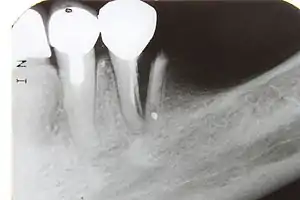

Предложенная Vertucci классификация относится к каждому отдельному корню, поэтому в различных корнях многокорневых зубов могут встречаются любые комбинации типов. Следует подчеркнуть, что данная классификация даёт весьма грубую и приблизительную схему возможных вариантов систем корневых каналов. Таким образом, представленные схемы на практике могут отличаться вариабельностью, встречаться в разных комбинациях, создавая весьма сложную топографию системы корневых каналов. Особую настороженность должны вызывать у клиницистов случаи наличия множественных апикальных отверстий, имеющие немаловажное значение в возникновении возможных осложнений после проведения эндодонтического вмешательства[3]. Именно поэтому практикующие врачи-стоматологи перед началом процедуры депульпирования проводят рентгенографическое обследование, позволяющее достоверно определить тип и количество корневых каналов в зубе[2].

- витальная экстирпация — при отсутствии выраженных воспалительных явлений, переходящих в периодонт, удаление сосудисто-нервного пучка и его обтурация проводится под анестезией в одно посещение. В канале оставляют лекарство (для антисептики и снятия воспаления). В процессе лечения необходимо сделать как минимум 2 рентгеновских снимка: первый — до начала лечения (для оценки длины и структуры каналов), а второй — после (для оценки качества пломбирования каналов).

Воспалительный процесс будет неизменно и планомерно разрушать слои зуба, провоцируя нестерпимую боль и неприятные последствия, главным из которых может стать потеря зуба. Кроме того, в некоторых случаях может потребоваться резекция корня или перепломбировка корневых каналов зуба. При этом основной задачей стоматолога является максимально полное заполнение канала корня пломбировочным материалом, предотвращающим возможное появление воспаления в дальнейшем. С этой целью широко применяются определённые пломбировочные составы, в состав которых добавлены антисептики. Для достижения поставленной цели в современных реалиях зачастую практикуются механические, а также медикаментозные методы. Механическая обработка корневых каналов может осуществляться при помощи соответствующих инструментов и современного оборудования, вплоть до эндодонтических моторов и так далее. В процессе медикаментозной распломбировки корневых каналов используют препараты, изготовленные на основе органических растворителей, которые способны изменять структуру пломбы. Альтернативным способом распломбировки каналов, заполненных цементом является использование специальных ультразвуковых эндонасадок, с помощью которых пломба удаляется за одно посещение стоматолога. Этот метод широко применяется в случаях, когда анкерный штифт не был установлен одномоментно с обтурацией корневого канала для распломбировки ранее вылеченного зуба под анкерный штифт для последующей реставрации коронки. Выполнение такой операции требует особой аккуратности, поскольку для последующей установки штифта необходимо сохранить часть пломбы, которая должна герметично закрывать верхушку корневого канала[10].